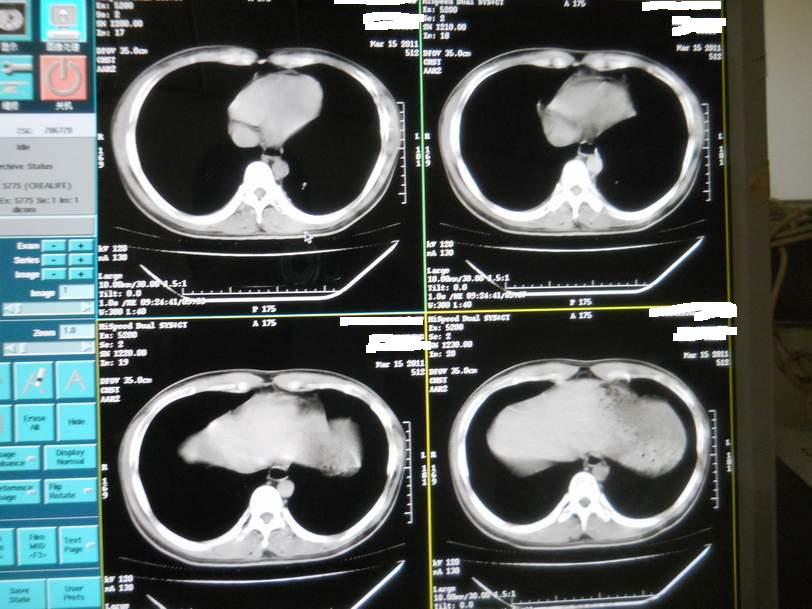

肺霉菌感染

男,22岁,一年前诊断马尔菲尼青霉菌感染,多次复查CT。多次HIV阴性。最近两次CT图片。有实验室结果。

最近实验室检查结果:霉菌感染。